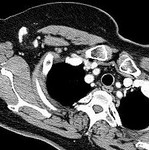

[画像診断]乳癌所属リンパ節の名称とレベル[基礎] 2011-01-27